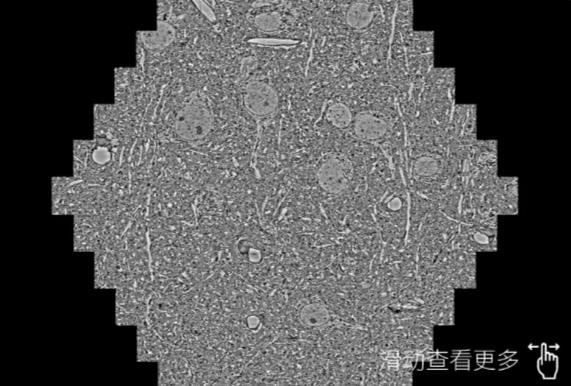

鼠脑切片。左图使用北屯蔡司北屯扫描电镜MultiSEM706对165μmx143pm面积区域成像,耗时仅需1.5秒。右图为鼠脑切片中30μm区域放大效果。样品由芝加哥大学B.Kasthuri提供。

使用蔡司高速北屯扫描电镜MultiSEM对1mm²人脑皮层组织进行高分辨成像,并对其中的各种细胞结构进行三维重构分析。左图展示了2x3mm²组织平面中锥体神经元的三维重构效果。右图显示了局部体积神经元三维重构。图像由哈佛大学chtman实验室提供,渲染图由D. Berger 制作。